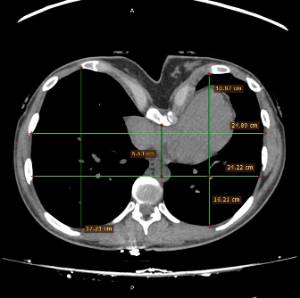

Los datos médicos del paciente, más la exploración clínica realizada por el equipo de cirugía, junto a un análisis pormenorizado de las imágenes del TAC y las reconstrucciones digitales en 3D de cada tórax realizadas conjuntamente con el equipo de ingenieros de Ventura Medical Technologies, son la base para determinar si la técnica Pectus Up está indicada y como se debe proceder en cada uno de los pacientes.

Con estos datos se selecciona el implante que mejor se ajustar a la anatomía de cada tórax, la ubicación exacta del sistema de elevación y, a su vez, proporciona al equipo quirúrgico un detalle de los pasos a tener en cuenta para llevar a cabo una correcta implantación.

Pectus Excavatum Pectus Excavatum Asimétrico Índice de Asimetría 0.6 (+R/-L)(|AI|> 0.05 Asimétrico) Índice de Haller 4.5 (HI >3.5) Índice de Corrección 49.13% Rotación esternal 18.1 ° (a la derecha)

Informe de evaluación del TAC de un paciente enviada al cirujano